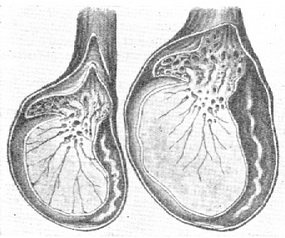

Маленькие яички

Уменьшение яичек может быть как односторонним так и двусторонним.

В норме размер яичек у взрослого мужчины составляет в длину от 4 до 6 см, а ширина колеблется от 2 до 3,5 см. Объем в норме составляет 12-30 см.куб. Размер яичек у мальчиков меняется в ходе взросления. Данные цифры являются относительными и незначительные отклонения, как в одну, так и в другую сторону могут быть вариантом нормы.

Заподозрить уменьшение размеров одного или обоих яичек врач может уже на этапе осмотра, во время пальпации. Уточнить размеры помогает УЗИ органов мошонки. Следует помнить о том, что врач делает выводы о размере тестикул только в комплексе с результатами гормонального обследования (тестостерон, эстрадиол, пролактин, ФСГ, ЛГ...) и параметрами спермограммы.